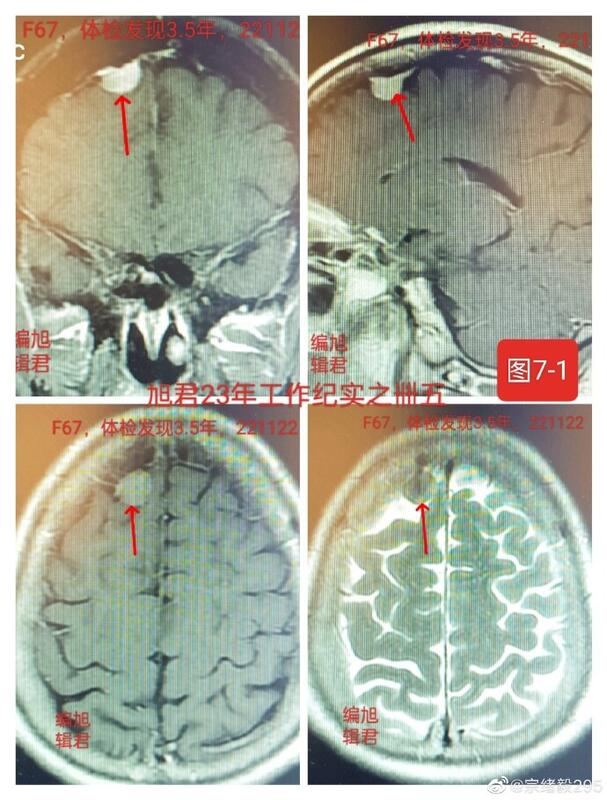

图7,1-2,某患者68岁,体检发现四年,近半年复查无变化,与首次发现报告,亦无变化。

图7-1

图7-2